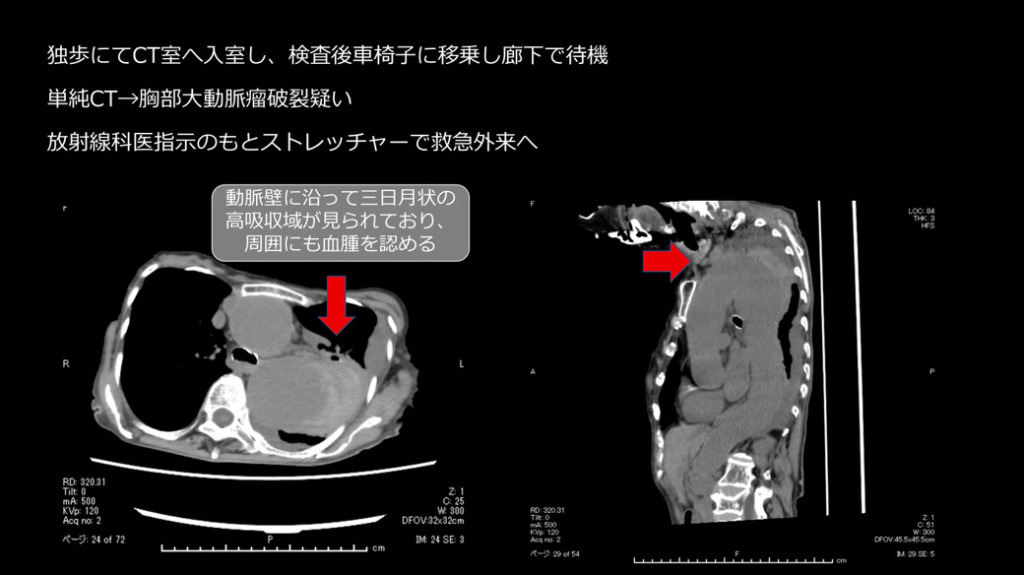

独歩にてCT室へ入室し、検査後車椅子に移乗し廊下で待機。(痛みを聞いても痛くはないと返事あり。)

単純CTで胸部大動脈瘤破裂疑いとなり、放射線科医指示のもとストレッチャーで救急外来へ移動しました。

胸部大動脈の著明な拡張と、その周囲に高吸収域を認める(大動脈破裂、contained ruptureを示唆)。

大動脈が大きいのと周囲に高吸収域を認めます。high attenuating crescent signと言われるもので、

これを見た時には大動脈の破裂を疑うべきです。やっぱり寝台から下ろすのはちょっと良くないかなと思います。

大動脈というのは基本的に横断面では丸いものなので、この辺縁を追っかけていくと一部が突出っていうのは異常な突出なので、ここはもう出血・血種がここにできているんじゃないかなっというのは想像できると思います。

あと、胸水も普通の胸水とは違って凹凸状に、肺を押すような感じで、CT値も若干高いことから血性胸水なの かもしれないというのを推測することができます。